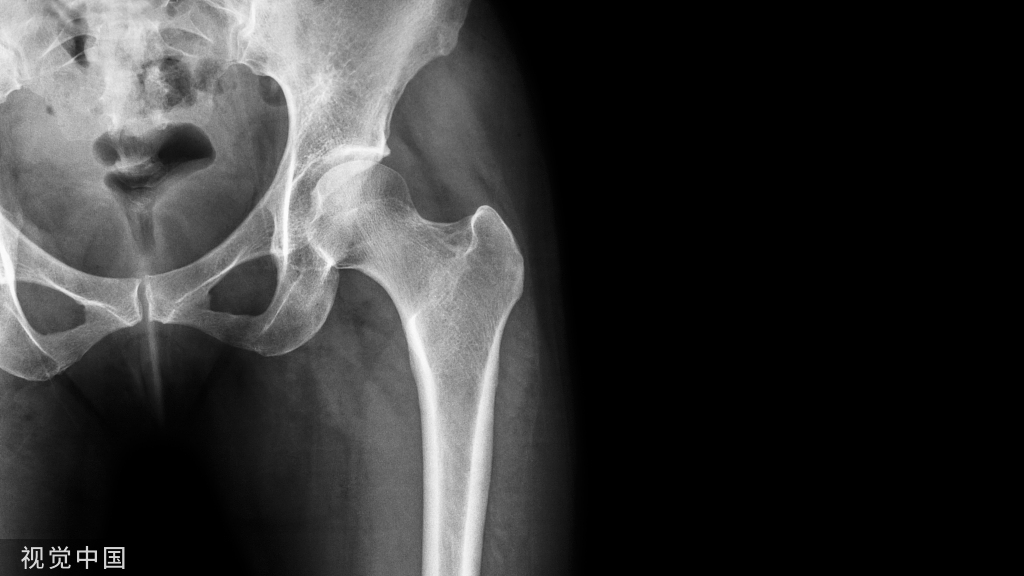

骨折畸形愈合的截骨矫形手术

此法可极大的简化截骨矫形手术过程,如下图:

最后为该患者矫形术后的下肢全长位片,患肢力线恢复满意